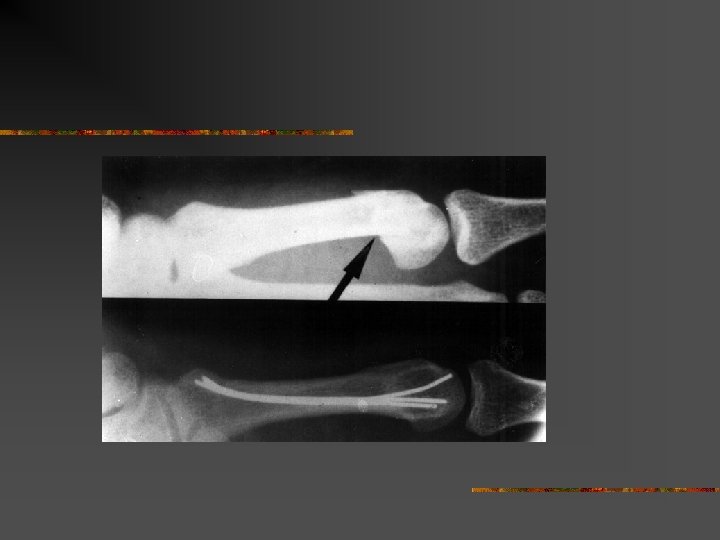

Le doigt en maillet n n Désinsertion de l’extenseur sur P 3 Arrachement osseux parfois

Le doigt en maillet

Traitement n n n Orthopédique+++ Attelle en extension pendant 6 semaines nuit et jour Puis 15 jours la nuit